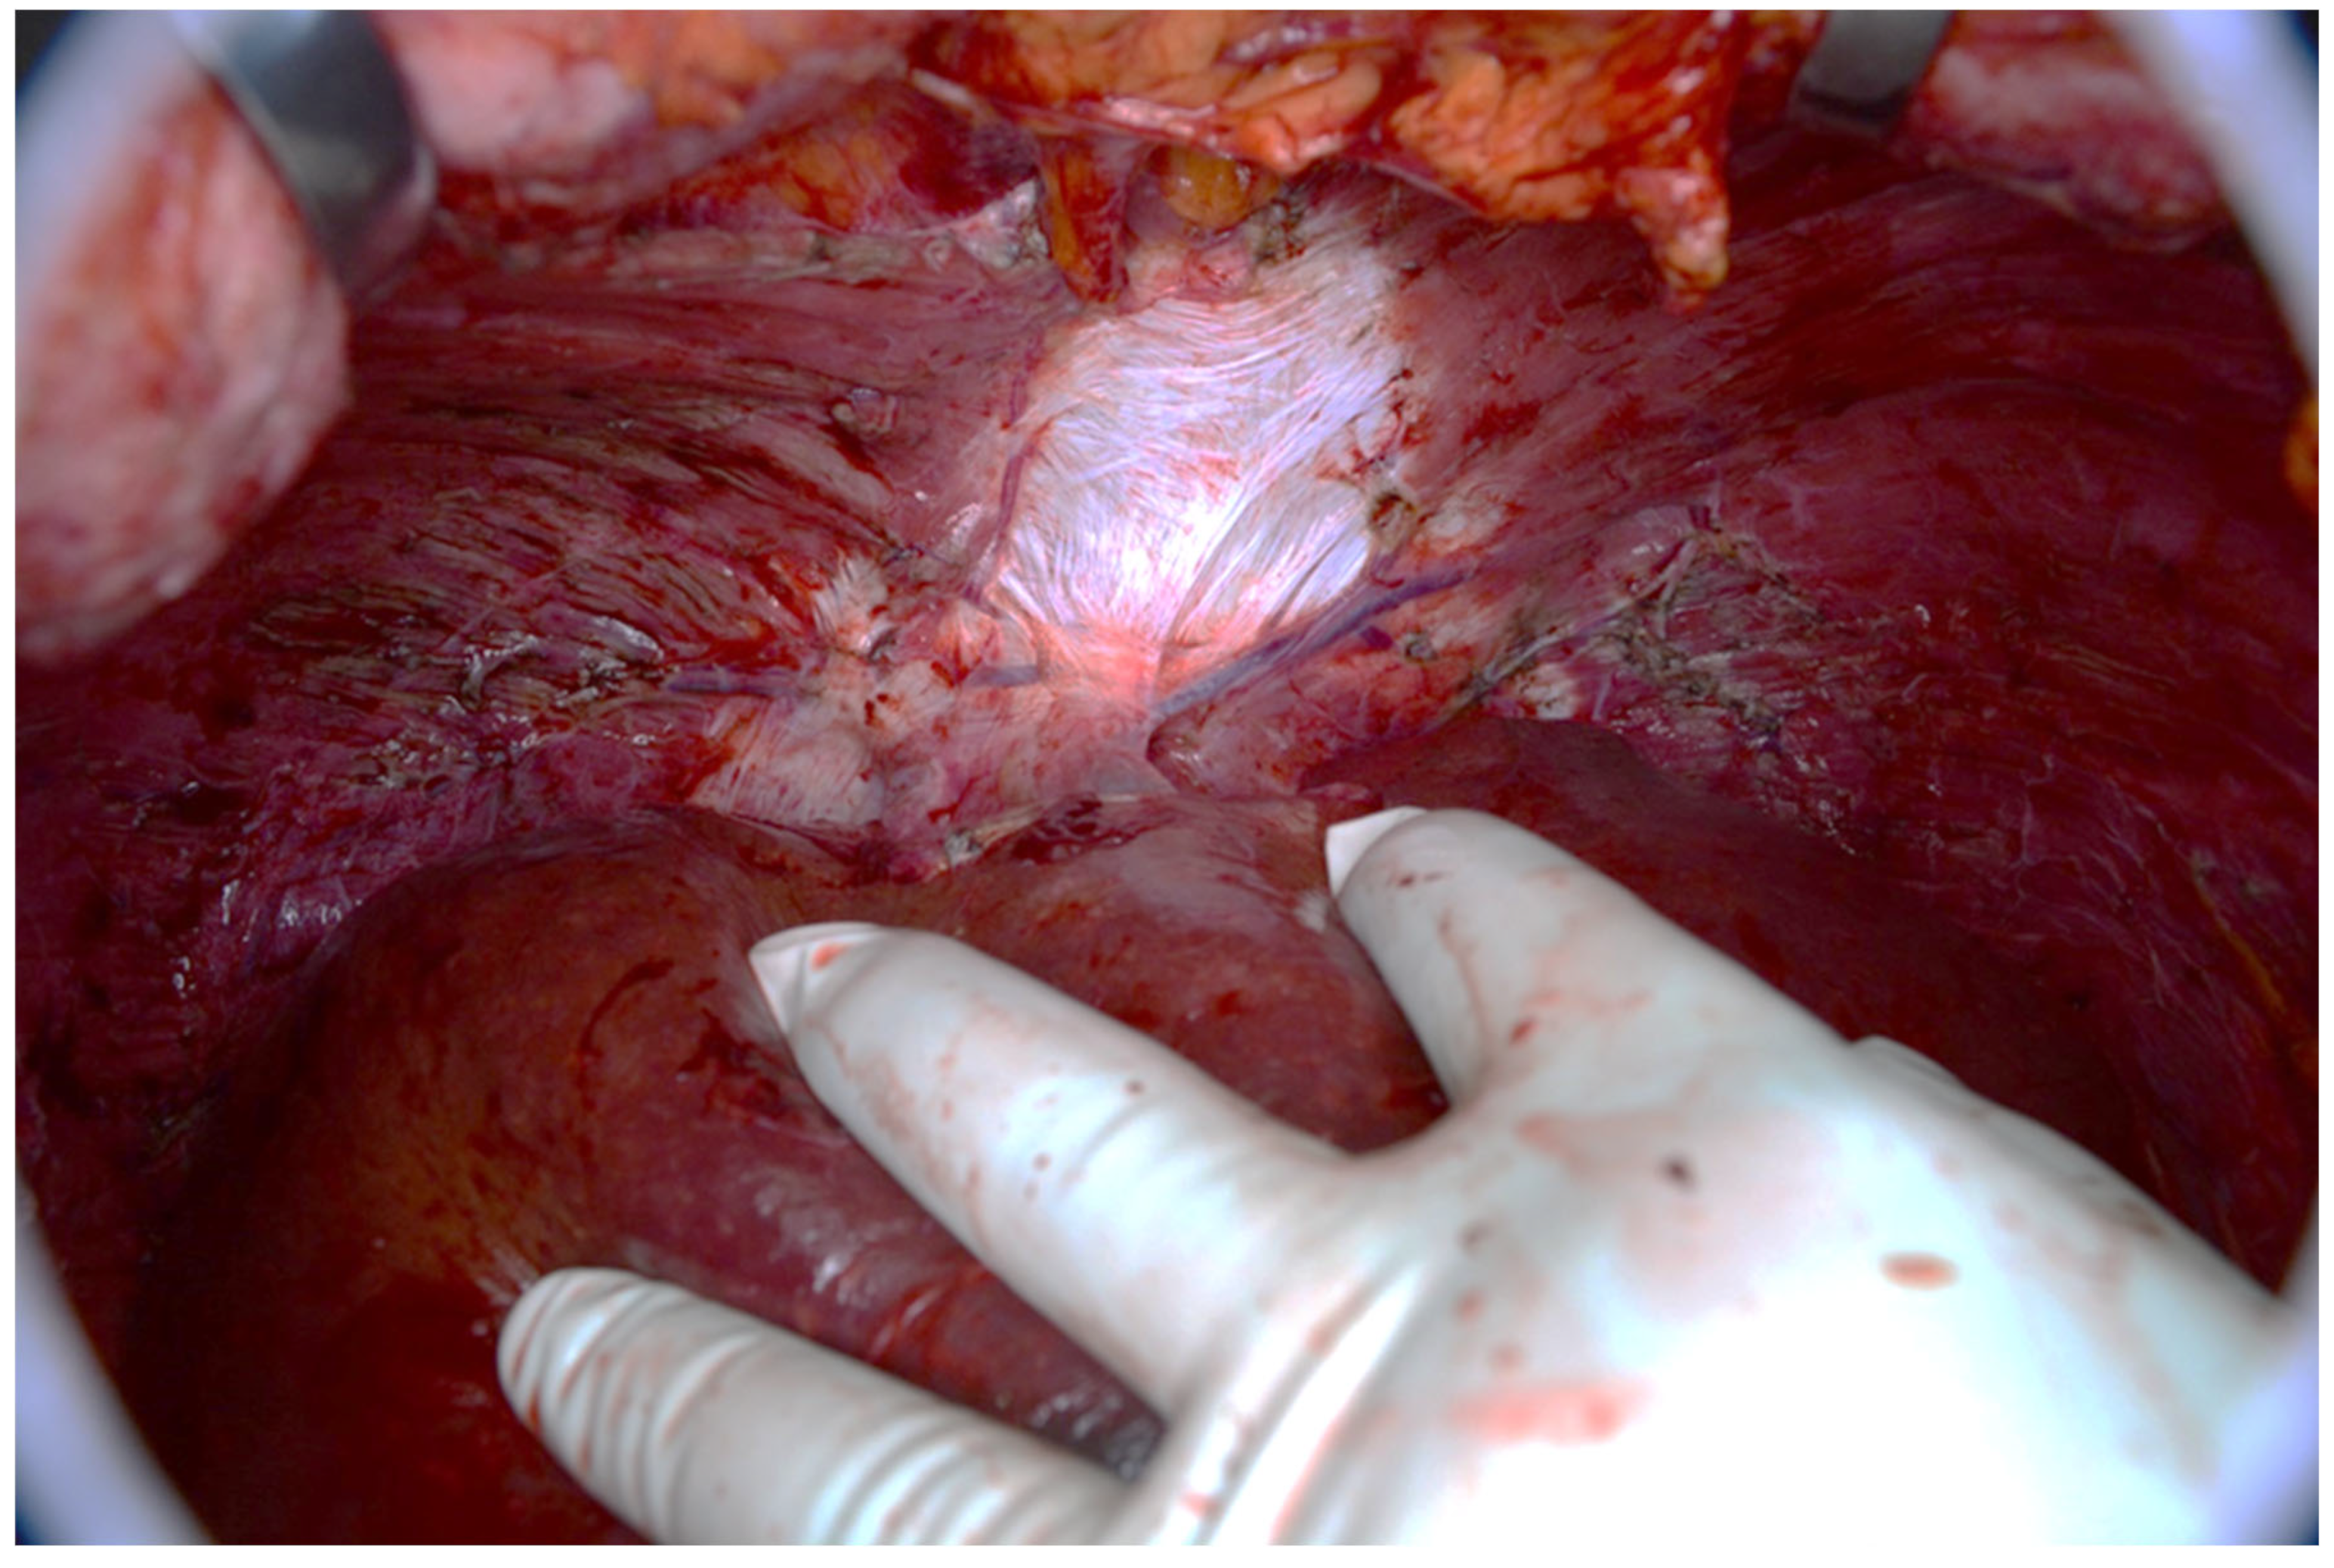

Figure 17. Intraoperative view of the abdominal cavity. The omentum contains many tumors.

Patients with a misdiagnosed rupture of the mucocele may develop pseudomyxoma peritonei. It is characterized by the presence of an abundant gelatinous substance in the abdomen. Diffuse, progressive, and abundant mucin-containing tumor cells are typical of this disease [2] (Figure 11, Figure 12, Figure 13, Figure 14, Figure 15 and Figure 16). The interval between rupture and advanced disease is several years. In our clinical series, the interval was about 5 years. In the literature, we found a wide range of this interval from 12 months to 10 years [9,10]. The natural history of PMP revolves around the “redistribution phenomenon”, whereby mucinous tumor cells accumulate in the Douglas pouch, in the diaphragm (more on the right), and the small and large omentum (Figure 17). The small intestine is less involved [4]. Pseudomyxoma peritonei is a slowly progressing disease, which fills the peritoneal cavity over time. There are several classifications of pseudomyxoma. The most commonly used is the PSOGI classification [2]. Mucinous accumulation progresses to malnutrition, bowel obstruction, and respiratory compromise. Rarely, the tumor may spread to the pleural cavity. This has been described in 5.4% of cases. It may occur spontaneously or as a result of diaphragmatic injury during cytoreduction [8,11].

Figure 11, Figure 12, Figure 13, Figure 14 and Figure 15. Advanced stage of the disease. The abdomen is full of tumors and mucin. Typical signs are heterogeneous or hypodense masses in the form of lobules often with septa, which could be enhanced by contrast and could be associated with calcifications.